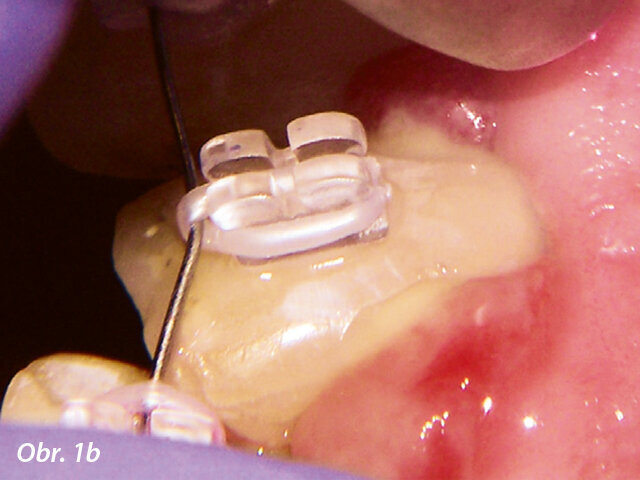

Gingivoplastika kvůli optimálnímu umístění zámku.